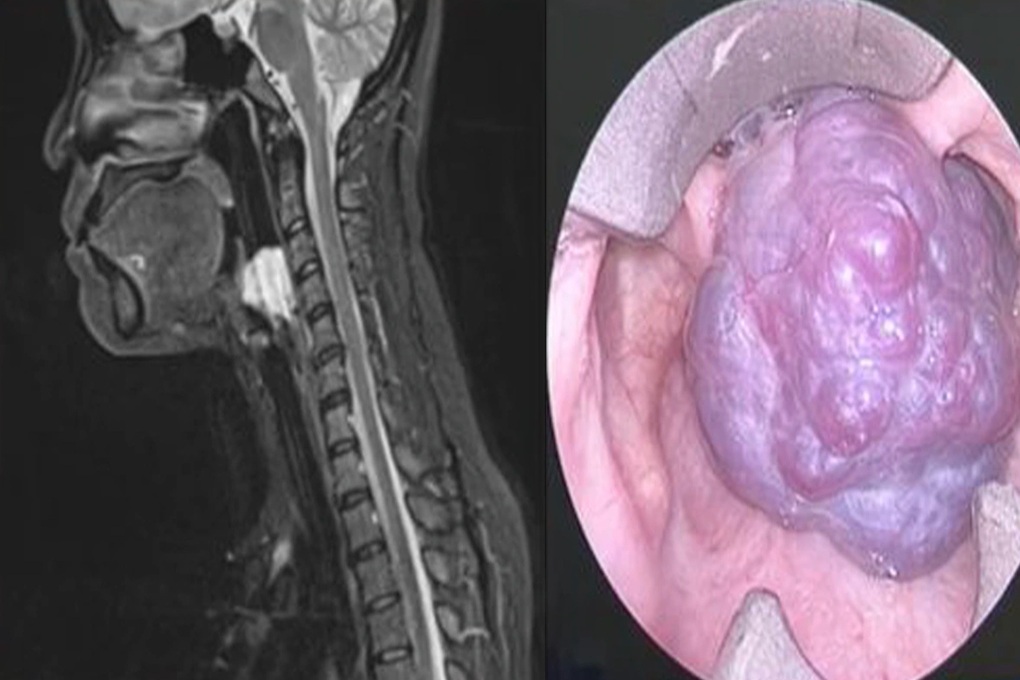

Qua kiểm tra chuyên sâu, bác sĩ Nguyễn Trương Khương ghi nhận đây là một trường hợp u máu lớn chiếm toàn bộ lòng thanh quản, gây khó thở và vướng khi nuốt – những triệu chứng dễ nhầm lẫn với các bệnh lý thông thường của đường hô hấp trên.

Hình ảnh khối u máu chiếm trọn thanh môn (Ảnh: BVCC).